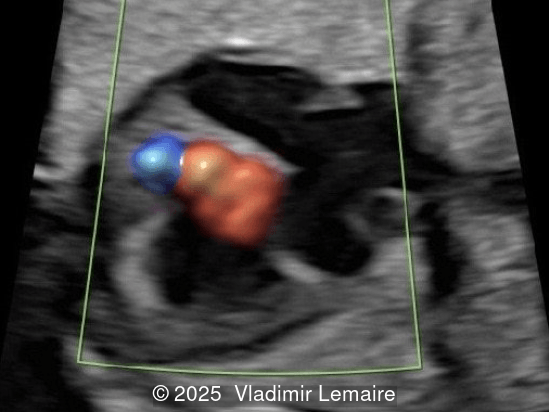

Right Ventricular outflow tract view.

Image 4 Right Ventricular outflow tract view.

Image 5 Right ventricular outflow tract view.

The size of the great vessel arising from the right ventricle should be evaluated for the presence of stenosis, which is a common association. The severity of right outflow tract obstruction directly correlates with the size of the right ventricle and the ventricular septal defect. Occasionally, pulmonary or aortic atresia can be found.

Color Doppler confirms the diagnosis on grayscale ultrasound, as it demonstrates the lack of blood flow across the tricuspid valve and a patent mitral valve. Due to increased blood flow across the mitral valve, aliasing is typically noted on color Doppler. Mitral valve regurgitation has been associated with a poor outcome. The right ventricular cavity is filled in late diastole from the left ventricle, through the ventricular septal defect. Left-to-right shunting across the ventricular septal defect can be seen on color Doppler. Color Doppler is helpful in the evaluation of flow across the great arteries. Flow across the pulmonary artery is generally antegrade. Pulmonary stenosis should be suspected when the vessel is diminutive in size rather than the demonstration of turbulent flow on color Doppler, which is typically absent in these cases.